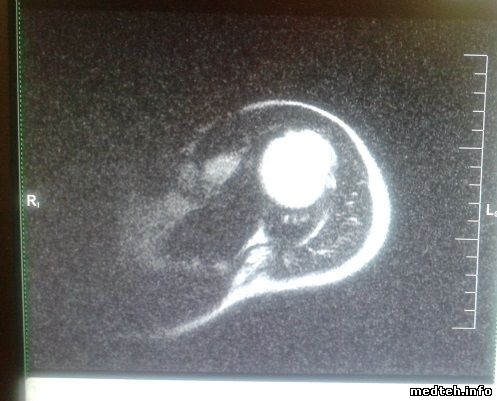

impact expert плечевая катушка cp flex large помехи при любом сканировании, очень похоже на низкое соотношение сигнал-шум, подскажите что может быть

5792681.jpg (76.4 Kb)